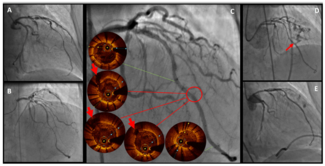

A 78-year-old woman admitted for anterior non-ST elevated myocardial infarction underwent coronary angiography, which showed a critical stenosis of the proximal and distal left anterior descending artery (LAD). After predilation, the distal...